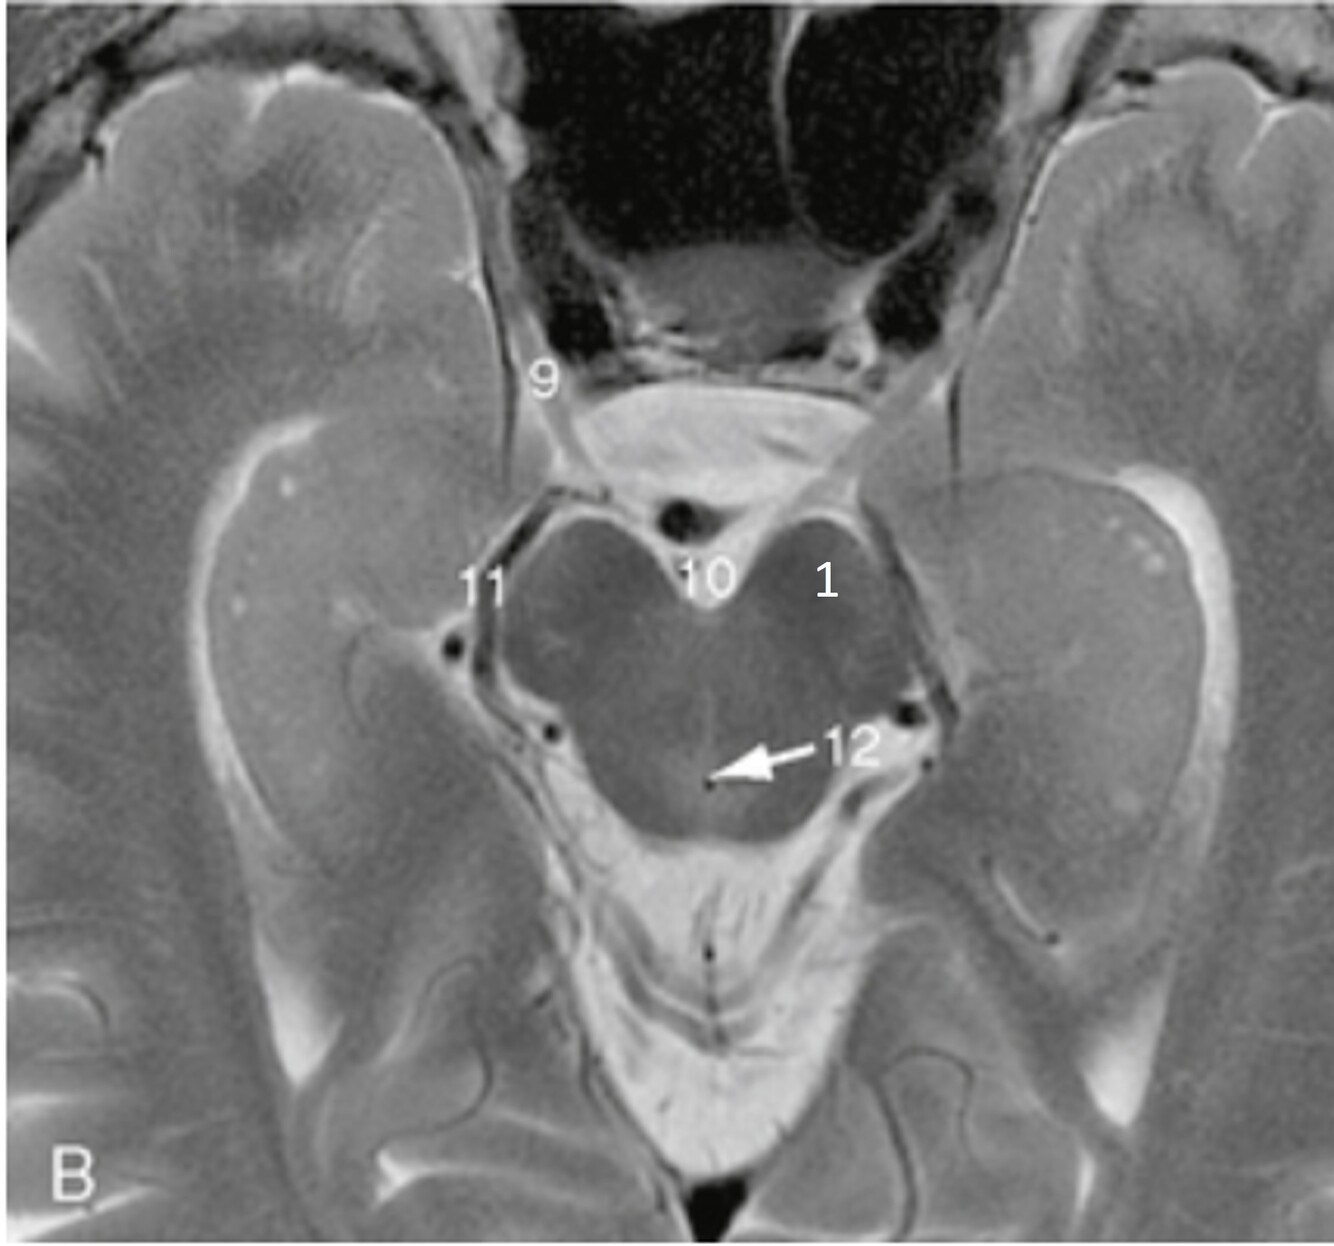

19

Q

Label 7-11

A

7=Rt Internal carotid artery

8=Optic chiasm

9=Pituitary gland

10-Lt lateral ventricle

11=Lt Cavernous sinus